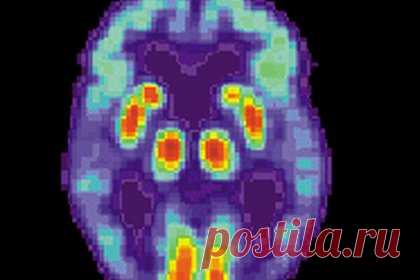

Ученые Университета Цинциннати подтверждают альтернативную гипотезу возникновения болезни Альцгеймера, согласно которой она вызвана снижением уровня определенного белка. Это противоречит преобладающей теории о накоплении бляшек, которая недавно была поставлена под сомнение. Об этом сообщается в статье, опубликованной в журнале Journal of Alzheimer's Disease. Общепринятое мнение гласило, что болезнь Альцгеймера вызывается накоплением амилоидных бляшек в головном мозге. Однако исследователи предположили, что бляшки являются следствием снижения уровня растворимого бета-амилоида в головном мозге. Эти уровни снижаются, потому что нормальный белок в условиях биологического, метаболического или инфекционного стресса трансформируется в аномальные амилоидные бляшки. Многие научные исследования и клинические испытания на протяжении многих лет были направлены на создание препаратов для уменьшения амилоидных бляшек в головном мозге, однако за исключением леканемаба ни одно из них не замедлило прогрессирование болезни Альцгеймера. Более того, препараты, снижавшие уровни растворимого бета-амилоида, лишь ухудшали клинические исходы. В новом исследовании ученые проанализировали уровни бета-амилоида у подгруппы пациентов с мутациями, вызывающими гиперэкспрессию амилоидных бляшек в головном мозге, что повышает риск болезни Альцгеймера. Однако в этой группе были обнаружены пациенты, у которых в мозге генерируются высокие уровни растворимого бета-амилоида, а риск развития деменции был снижен в течение трехлетнего периода. Было продемонстрировано, что при исходном уровне растворимого бета-амилоида в головном мозге выше 270 пикограммов на миллилитр люди могут сохранять когнитивное здоровье независимо от количества амилоидных бляшек в мозге. По словам ученых, леканемаб, антиамилоидный препарат, чья эффективность была показана в недавних клинических исследованиях, делает то, чего не делает большинство других антиамилоидных препаратов: помимо снижения уровня амилоида, он увеличивает уровень растворимого бета-амилоида.